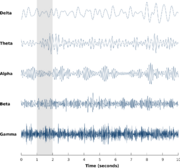

| 11:24, 1 April 2023 | EEG Brainwaves.png (file) |  |

418 KB | 1 | |